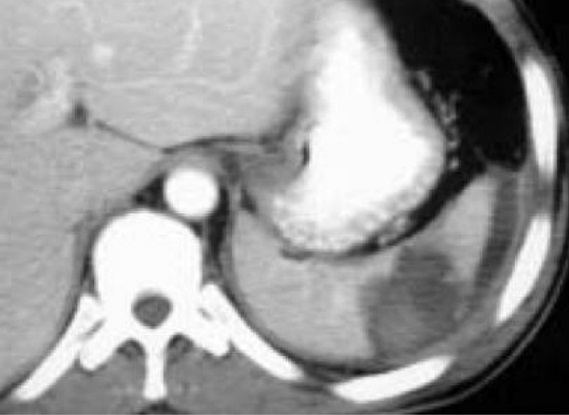

Image radiologique en

forme de coin * wegde sharpe ) au pole inferieure de

la rate d'une leucemie myeloide . Aspect

lesionnel est hypodense en form de coin a

bord nette et moins regulier , la rate est

tres volumineuse . Coupe coronal TDM plus

contrast intraveineuse phase veineuse . |

Image radiologique TDM d'une thrombose de

la veine splenique La region de

infartion est tres large , tres hypodense et 'la

rate est volumineuse Image radiologique TDM en

coupe axale phase veineuse |